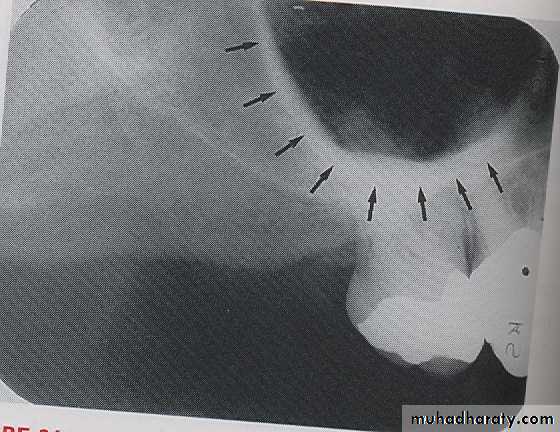

CORONOID PROCESS:

The coronoid process is a marked prominence of bone on the anterior ramus of mandible. Radiographically the coronoid process is not seen on mandibular periapical radiography but dose appears on maxillary periapical film as triangular radiopacity superimposed over the maxillary tuberosity region.